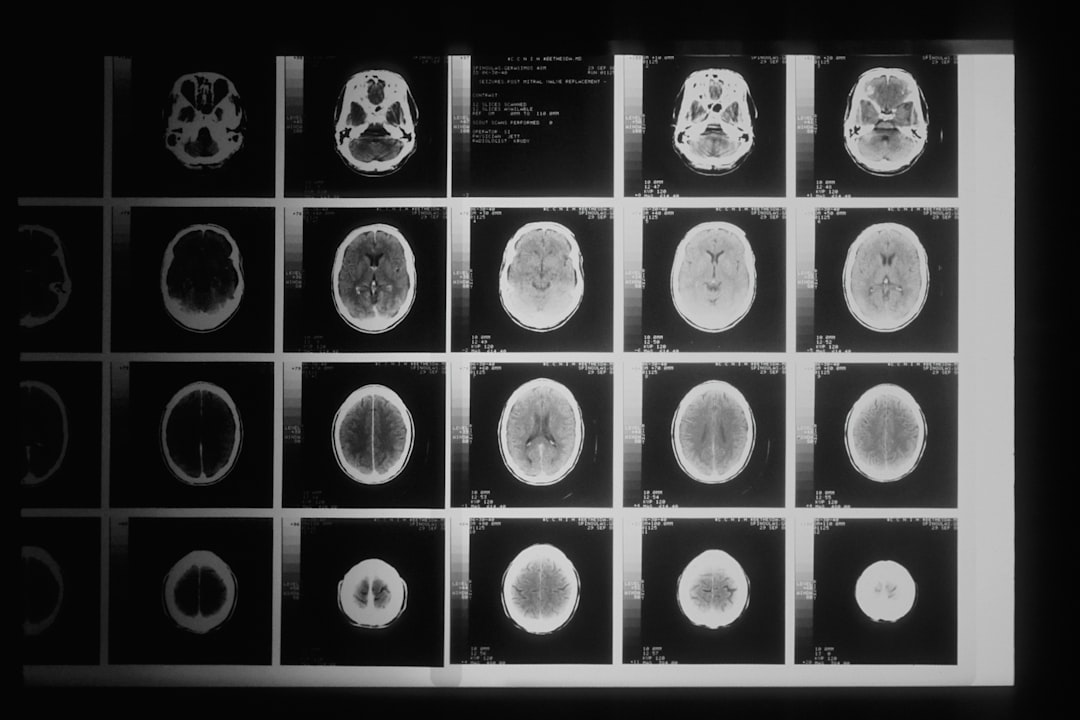

Diagnosen stilles vanligvis av en nevrolog basert på en grundig vurdering av symptomene dine og en fysisk undersøkelse. Det finnes ingen spesifikke tester for å bekrefte Parkinsons sykdom, men bildediagnostikk som MR eller PET-skanning kan brukes for å utelukke andre tilstander.